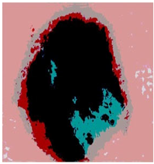

| Segmented Image | R | G | B |

|---|---|---|---|

![]() | ![]() | ![]() | ![]() |